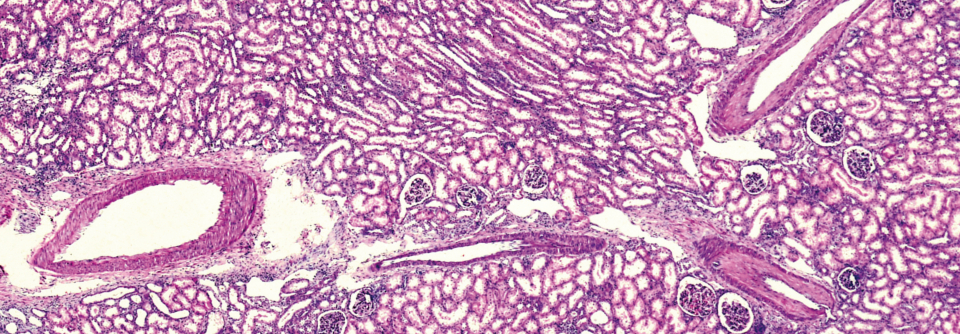

Die Minimal-change-Glomerulopathie ist die häufigste glomeruläre Erkrankung bei Kindern, beginnt aber auch bei bis zu 15 % der Betroffenen erst im Erwachsenenalter. Die Minimal-change-Glomerulopathie ist die häufigste glomeruläre Erkrankung bei Kindern, beginnt aber auch bei bis zu 15 % der Betroffenen erst im Erwachsenenalter. © DINESH MADUSANKA – stock.adobe.com

Plötzlich eine starke Proteinurie, keine Hämaturie und keine Entzündungszeichen im Urin: Das spricht für eine Minimal-change-Glomerulopathie. Diese Erkrankung ist zwar typisch für Kinder, kann sich aber auch bei Erwachsenen erstmals manifestieren, wie ein Fallbeispiel zeigt.